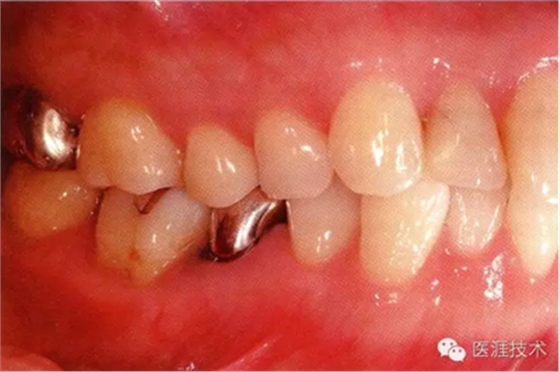

55歲牙周炎男性的臨床照片

55歲男性抽煙患者(1天20支、抽煙35年)。菌斑控制得不好。通過(guò)牙周探診,全頜有4~9mm的牙周袋,有1~3度的根分叉部病變。通過(guò)X光片觀察,上頜前牙中度牙槽骨吸收,其他地方有中度牙槽骨吸收。受吸煙影響,牙齦纖維性肥厚,呈紅黑色。牙齦幾乎沒(méi)有浮腫和發(fā)紅,所以這個(gè)病例是從外觀上無(wú)法預(yù)測(cè)病癥嚴(yán)重程度的病例。